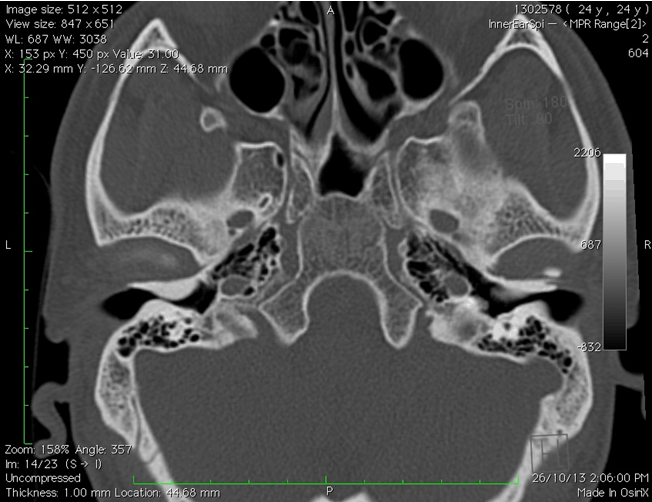

Following findings were noted on HRCT. Broad-based osseous overgrowth of external auditory canal bilaterally, were noted on axial CT images. (Figure 1). Sagittal CT images showed evidence of dense bony protuberances arising from the tympanic and the petrous bone into the external auditory canal space. This resulted in significant narrowing of the ear canal and thus conductive hearing loss bilaterally (Figure 2). On obtaining a detailed history, it was noted that the patient was a frequent swimmer. Thus, the diagnosis of surfer's ear was made. The patient was referred for surgical management of the exostoses.

Figure 1: High resolution computed tomography axial image of bilateral temporal region showing bony outgrowth in the external auditory canals.